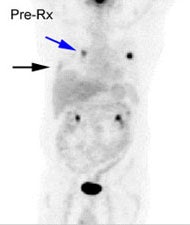

Chronic hyperglycemia:

The patient below presented for staging of a left lung

non-small cell lung cancer. The patient was a diabetic

and had a blood glucose of 206. Because of social

issues, it was elected to inject the patient and

perform the scan. The images obtained were of

excellent quality with marked uptake in the patients

left lung mass (blue arrow). Also, several less than 1

cm lymph nodes in the aorto-pulmonary window and

mediastinum were positive on the PET exam (black

arrows) and these had not been called prospectively on

the CT study. The patients chronic hyperglycem |